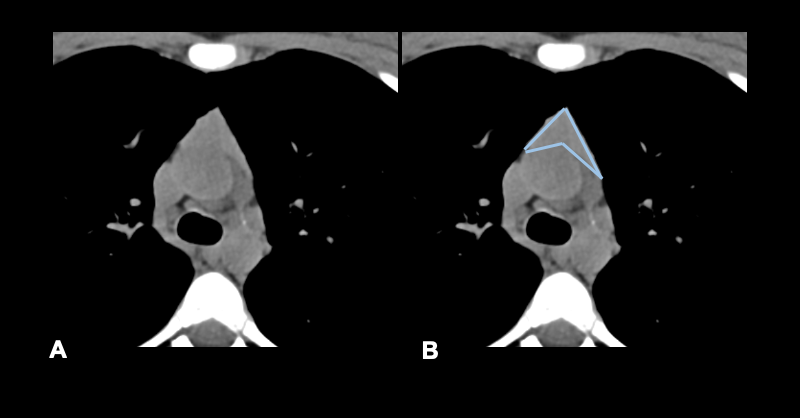

胸腺瘤在CT上通常表现为边界锐利、椭圆形的均质软组织肿块(图11-14)。偶尔,大的肿瘤可能显示钙化,出血区域,甚至坏死(图15)。局部浸润性疾病表现为不规则的肿瘤界面、胸膜结节和积液以及“滴状转移”[2]。

Thymomas in CT usually appear as a homogenous soft tissue mass with sharp borders and an oval shape (figures 11-14). Occasionally, large tumors may reveal calcifications, areas of hemorrhage, or even necrosis (figure 15). Locally invasive disease is suggested by irregular tumor interfaces, pleural nodules and effusion, and “drop metastases” [2].

图12:女性,65岁,重症肌无力。A-在右侧纵隔,我们观察到3厘米的软组织致密图像(黄色箭头)。胸腺瘤A型。Masaoka 2期。TNM pT1a Nx Mx。三个月后,病人接受了手术。在右侧心包断层图中,胸腺切除部位未显示疑似复发的结节图像(绿色箭头)。

Fig 12:Female, 65-years old with myasthenia gravis. A- In the right lateral mediastinum we observe an image of 3 cm of soft-tissue densification (yellow arrow). Thymoma type A. Masaoka stage IIa. TNM pT1a Nx Mx. B – Three months later, the patient underwent surgery. In the right pericardiac topography, the thymectomy site shows no nodular images suspected of recurrence (green arrow).